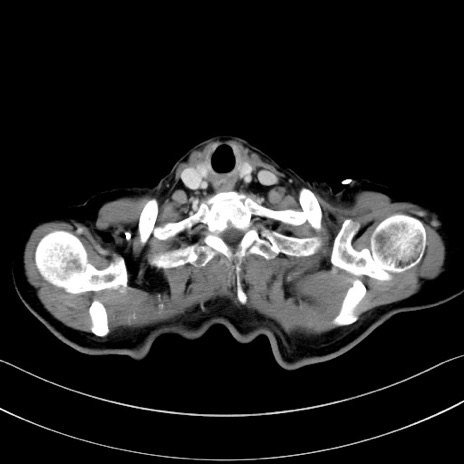

症例28(横断像)

【症例】60歳代男性

【主訴】嘔吐

【現病歴】胃癌にて胃全摘後。食思不振が悪化し、夜中に嘔吐することがある。

【既往歴】胃癌、胃全摘、脾摘、胆摘後

【データ】WBC 5900、CRP 10.56